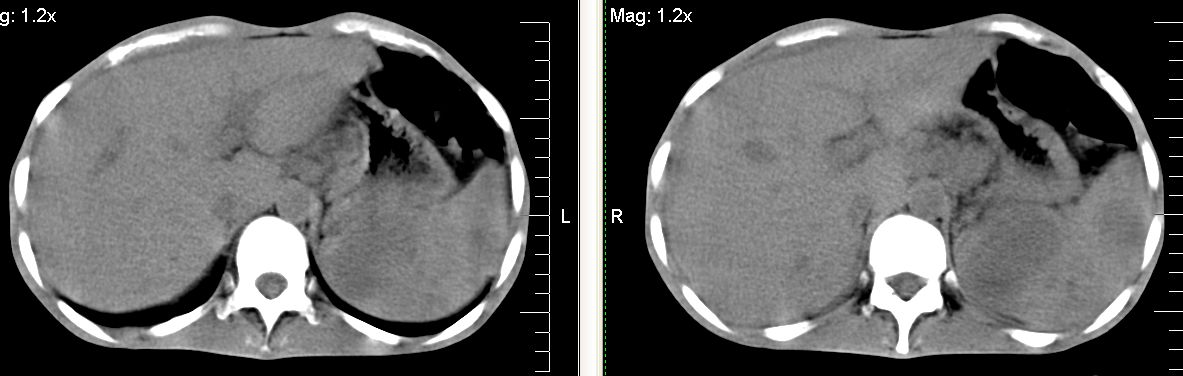

脾脏多发低密度灶,肠系膜及腹膜后见多发大小不等结节状影,右结肠旁沟见低密度影,结合病史考虑:脾结核,肠系膜及腹膜后淋巴结结核,少量腹水。

右侧结肠亦可见病变,腹膜后可见多发增大的淋巴结影,脾脏内示多个低密度结节灶,结合病史考虑结核性病变。

脾脏多发低密度灶,腹膜后及肠系膜根部多发淋巴结淋巴结肿大并部分相互融合,考虑tb.图象窗宽\\窗位没调整好,不清晰,另外,肠道准备亦不理想.

脾脏多发低密度灶,左侧肾上腺见块状病灶,密度不均,盲肠升结肠肠壁明显增厚,左下腹似可见肠壁增厚,肠系膜及腹膜后见多发大小不等结节状影,右结肠旁沟见低密度影,1淋巴瘤可能大,2结合病史考虑:脾结核,左侧肾上腺结核,肠系膜及腹膜后淋巴结结核,少量腹水待除外,